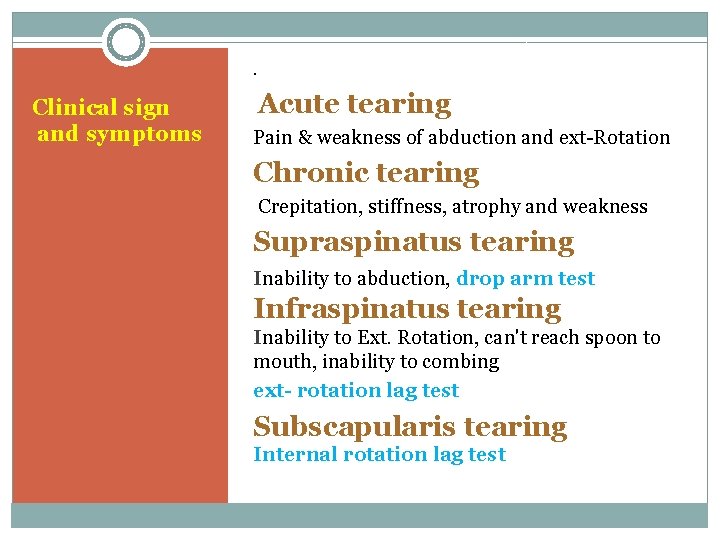

. Clinical sign and symptoms Acute tearing Pain & weakness of abduction and ext-Rotation Chronic tearing Crepitation, stiffness, atrophy and weakness Supraspinatus tearing Inability to abduction, drop arm test Infraspinatus tearing Inability to Ext. Rotation, can't reach spoon to mouth, inability to combing ext- rotation lag test Subscapularis tearing Internal rotation lag test